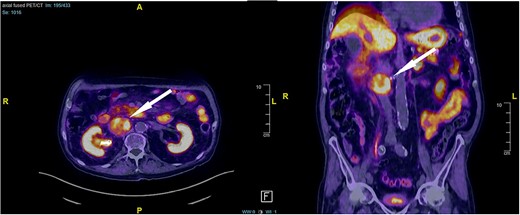

An 87-year-old male Caucasian patient with a history of cardiac co-morbidities, diabetes mellitus type 2, and chronic kidney disease stage 4 was referred to our hospital for clinical evaluation and a non-contrast abdominal–pelvic CT scan because of right side pain with a history of kidney stone disease, with recurrent ureteral stones. The CT scan showed a small distal ureteral stone on the right side without the need for surgical intervention. Incidentally, he had a retroperitoneal mass (4.4 × 4 × 4 cm) posterior to the inferior vena cava, with compression on the inferior vena cava and the right renal artery (Fig. 1). Our radiologist classified this unexpected incidental finding as a possible neuroendocrine tumor, with the recommendation to perform a DOTATE-PET/CT scan. The DOTATE-PET/CT showed a sizeable retrocaval mass with edge-accentuated radionuclide storage, compatible with a paraganglioma or a lymph node metastasis of a neuroendocrine tumor (Fig. 2). The ultimate etiology remained unclear, despite the radiological scans. Our blood tests showed a normal level of hormones in the blood and urine, excluding hormonally active tumors. The only noticeable value in the blood was the elevated creatinine as a part of the chronic kidney disease. One of our assumptions was that the tumor compression on the renal artery impacts the patient’s kidney function. The patient reported no remarkable symptoms.

CT scan findings, 4.5 × 4 × 4 cm right retroperitoneal mass posterior to the inferior vena cava, with compression on the inferior vena cava and the right renal artery (arrow).